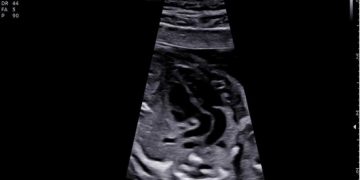

Casi del Mese di Dicembre 2024

Cari soci, finalmente on line le soluzioni dei casi del mese di Dicembre. Grazie a Sara Zullino e Mara Albanese!! Caso 1 - video [pdf-embedder url="https://www.sieog.it/wp-content/uploads/2024/12/Casodelmese_Dicembre2024caso-risposte_gineco.pdf"...